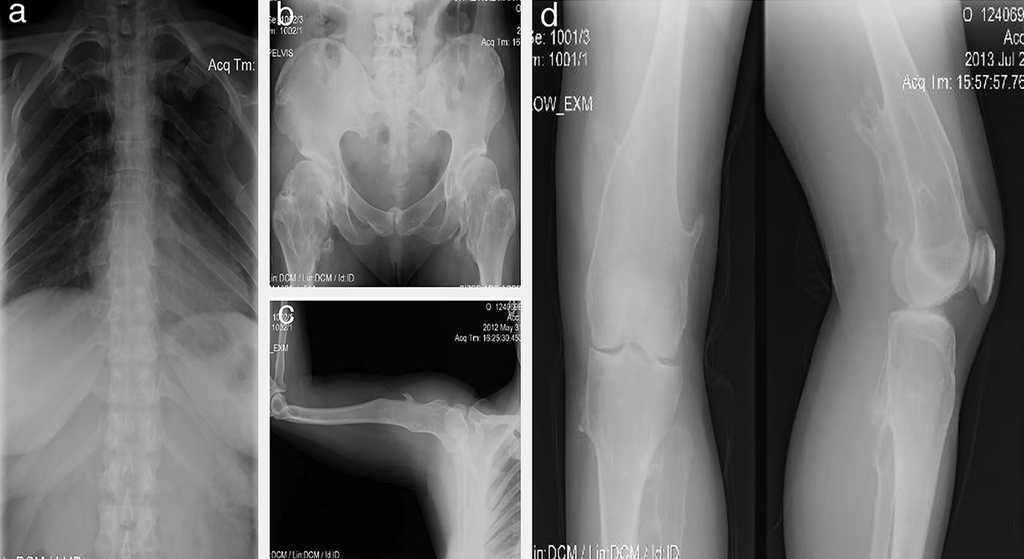

Paciente de sexo femenino, de 40 años de edad; desde que nació los padres percibieron muchos chasquidos articulares al cargarla, sin dolor aparente. A los 3 años de edad se detectó protuberancia incapacitante en rodilla izquierda que le producía dolor al caminar, por lo que requirió cirugía. A los 16 años desarrolló una deformidad en los tobillos (región maleolar externa de 4 × 4 × 3 cm y región de tibia) que le producía dolor, por lo que ameritó cirugía correctiva. A los 20 años presentó engrosamiento y deformidad de las muñecas, que llegó a medir 4 × 5 × 2 cm. Al final de su crecimiento óseo se determinó que la longitud del brazo derecho era 2 cm mayor que la del izquierdo (Fig. 2).

Figura 2 Caso 1 (II2). Paciente femenino de 40 años (madre) que presenta excrecencias óseas (exostosis) con manifestaciones en la unión esterno-costal de las primeras costillas y la parte superior del arco costal posterior (a), protuberancias óseas en cuellos femorales y región intertrocantérica con deformidad ósea (b), exostosis en región proximal de húmero (c) y tercio distal de fémur bilateral en región postero-medial y en borde postero-externo de tibia izquierda (d).